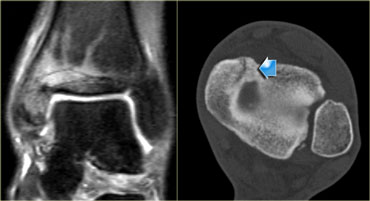

Grade 4 stress fracture of the navicular bone. T1WI and CT (axial image and coronal reconstruction) Grade 4 stress fracture of the navicular bone. T1WI and CT (axial image and coronal reconstruction)

On the left a 27-year old soccer player in the highest league of amateur football.

He suffered from midfoot pain with a recent increase in complaints.

T1WI shows a definite fracture line in the navicular bone, indicating a grade 4 stress fracture.

Corresponding CT shows a fracture line and sclerosis on the axial images and coronal reconstructions.